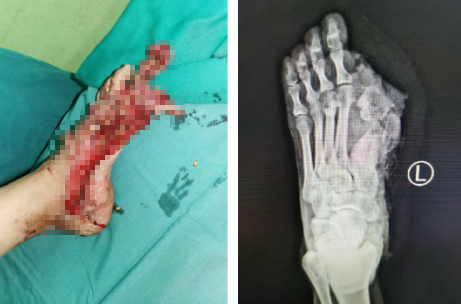

32岁的崔女士,左脚遭机械碾压,大踇脚趾连同半个脚掌被“碾烂”,这只脚还能恢复“原样”,正常走路吗?来到betway在线登陆急诊时,患者和家人都面露惨色,一再向医生寻求“保证”。

急诊足踝科的陈占斌主治医生接诊,立即给患者仔细检查,评估病情。患者左脚半个脚掌,大踇脚趾与脚掌连接的第一跖列完全毁损,创面污染严重。

严谨而迅速的术前准备后,陈占斌、崔运动手术小组为患者进行了细致全面的清创+抗生素骨水泥填充手术,过程顺利。